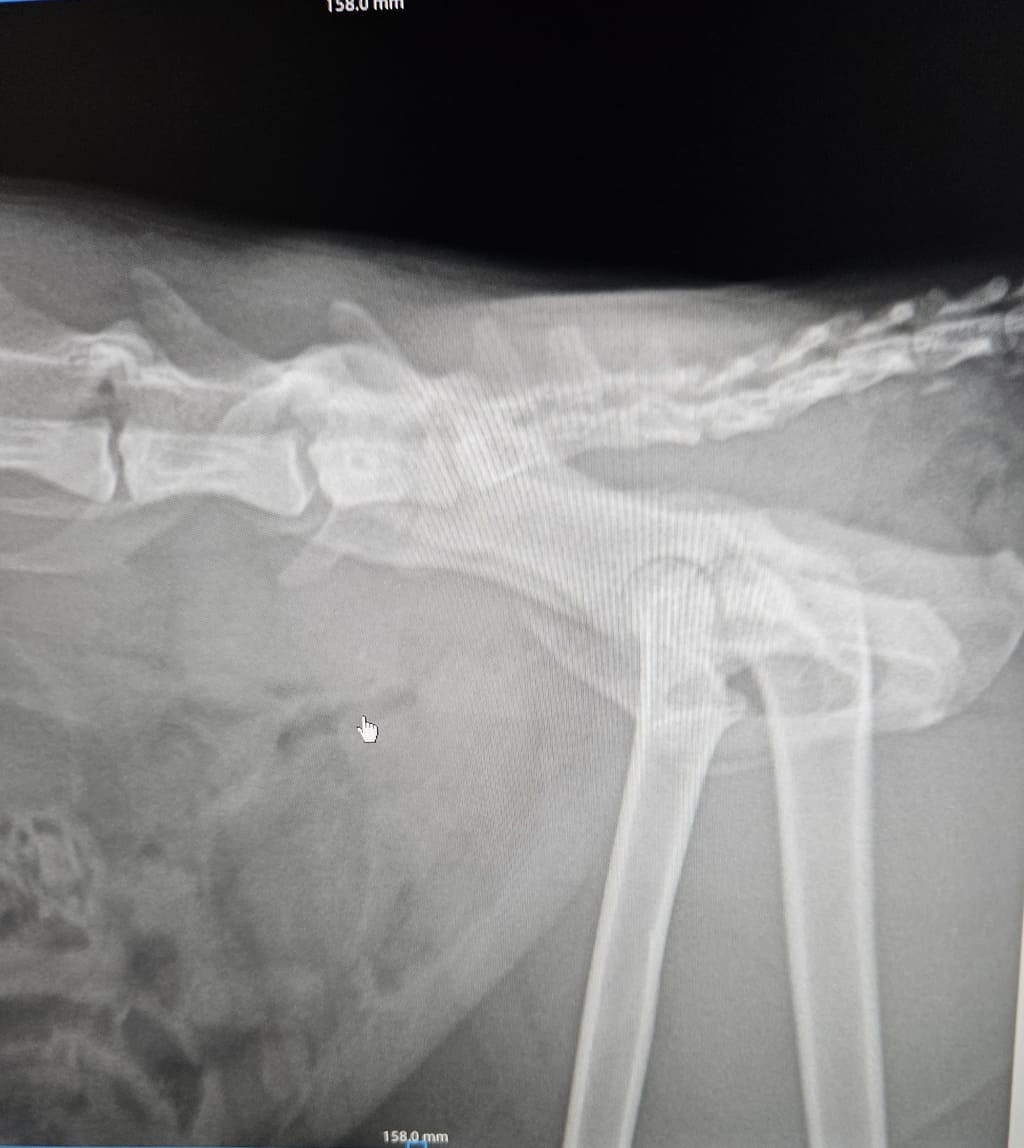

Le condizioni del povero micio

Il micio trovato investito e abbandonato in strada dovrà subire un intervento. Ha anche la vescica lacerata. Abbiamo bisogno di soldi, da soli non possiamo farcela, la cifra è alta.